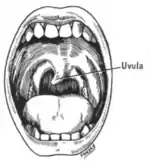

Oral sensation, taste, and salivation (IX)

The glossopharyngeal nerve (IX) supplies the stylopharyngeus muscle and provides sensation to the oropharynx and back of the tongue.[3] The glossopharyngeal nerve also provides parasympathetic input to the parotid gland.[3]

Damage to the nerve may cause failure of the gag reflex; a failure may also be seen in damage to the vagus nerve (X).[16]

A cranial nerve exam starts with observation of the patient, as some cranial nerve lesions may affect the symmetry of the eyes or face.[16] Vision may be tested by examining the visual fields, or by examining the retina with an ophthalmoscope, using a process known as funduscopy. Visual field testing may be used to pin-point structural lesions in the optic nerve, or further along the visual pathways.[17] Eye movement is tested and abnormalities such as nystagmus are observed for. The sensation of the face is tested, and patients are asked to perform different facial movements, such as puffing out of the cheeks. Hearing is checked by voice and tuning forks. The patient's uvula is examined. After performing a shrug and head turn, the patient's tongue function is assessed by various tongue movements.[16]